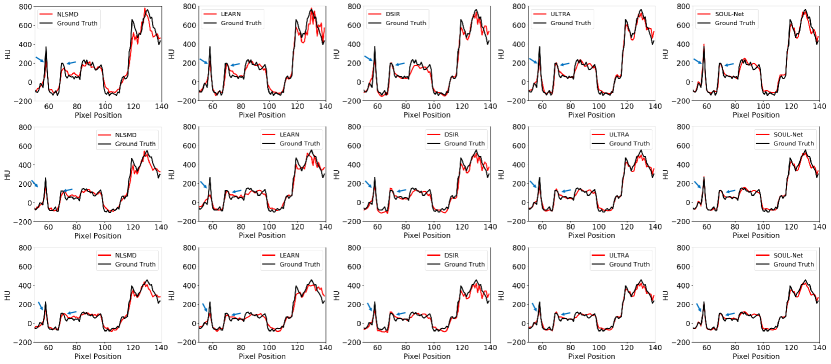

Fig. 5 shows the horizontal profiles of different results along the blue dashed line in the first row of Fig. 2. Two blue arrows indicate two sharp areas that can distinguish the ability in edge preservation for different methods . It is obvious that the proposed SOUL-Net has the closest results to the reference and achieves higher reconstruction accuracy than other methods. This is consistent with the results of our visual inspection.